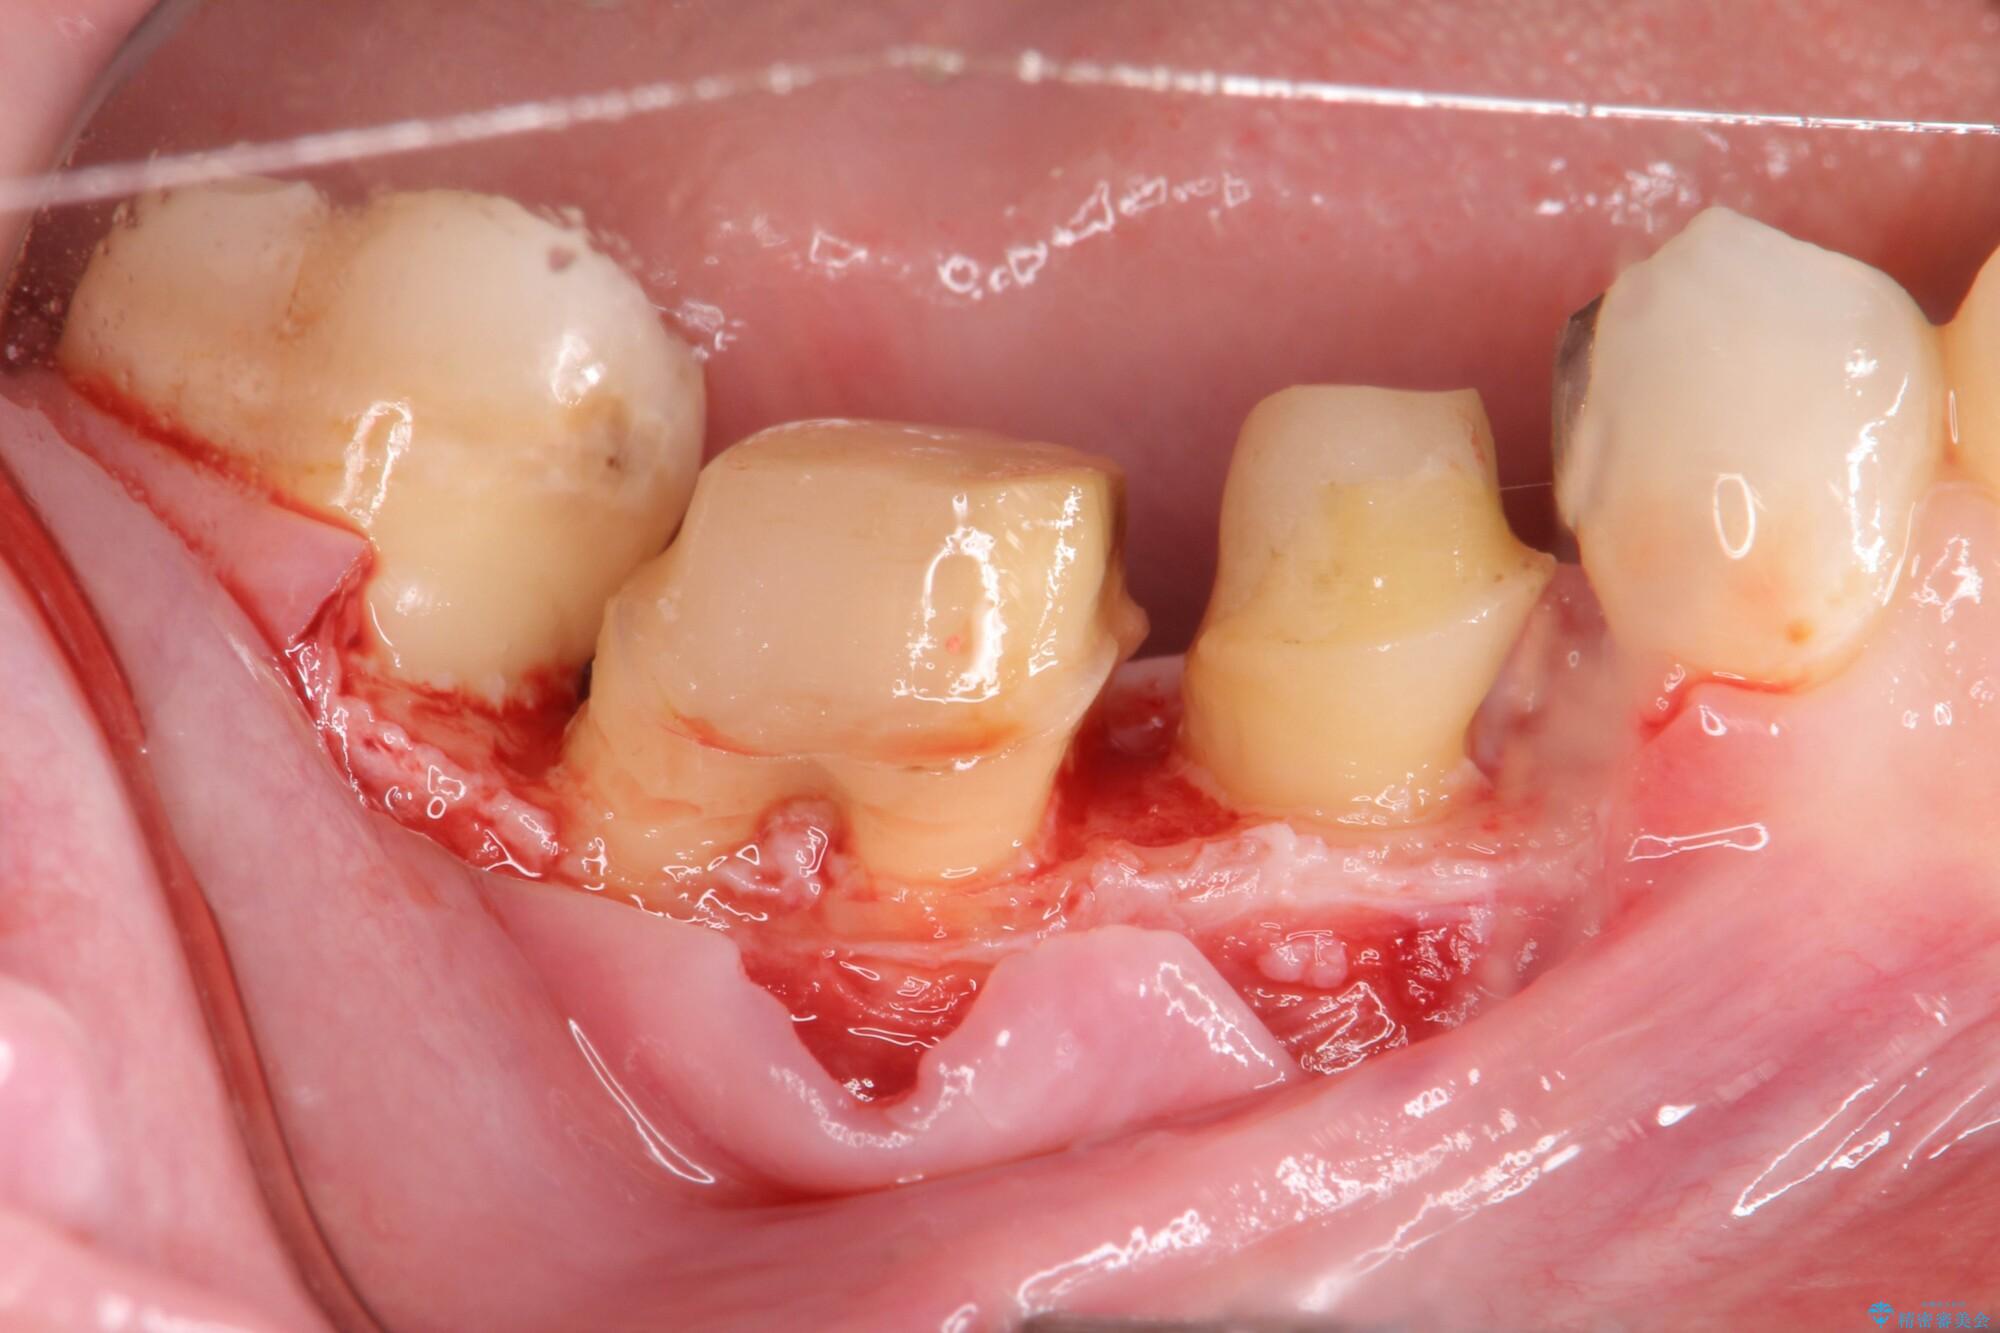

装着されていた清掃性の悪い銀歯を外すと、銀歯の下で歯ぐきよりも深い虫歯が再発していました。

虫歯を丁寧に除去し、歯周外科を用いて周囲の歯ぐきの炎症を除去します。その後、清掃性の高い精密なセラミック治療をおこなっていきます。

外科手術のため、術後に出血、痛みや腫れ、違和感を伴います

口腔内の状態によっては適応できないことがあります